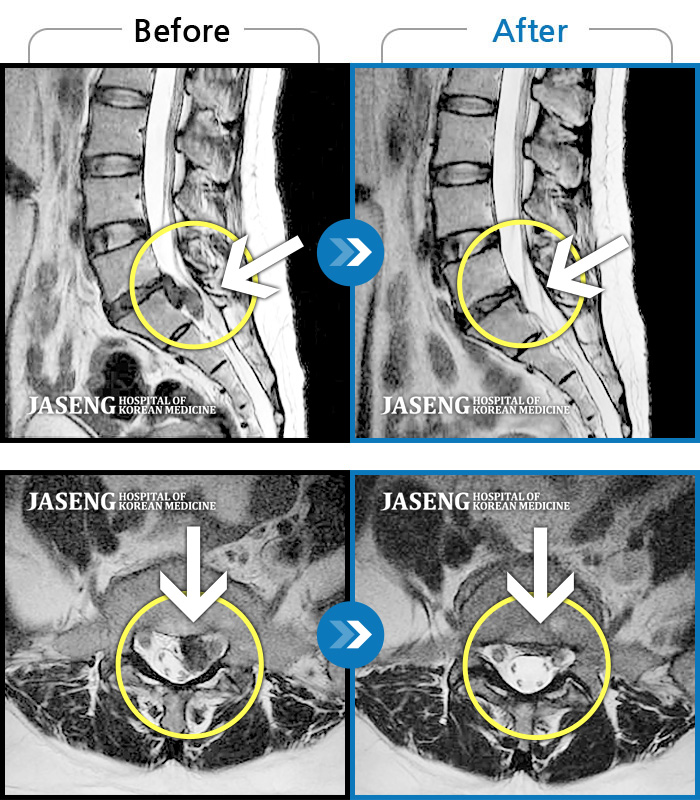

허리디스크

잠실 · 한상욱 원장

허리, 우측 엉치와 다리 후면 및 발끝까지 저림과 통증이 심하고 힘까지 빠진다.

촬영시기

2022.06.15 ~ 2022.11.11

2022.12.02